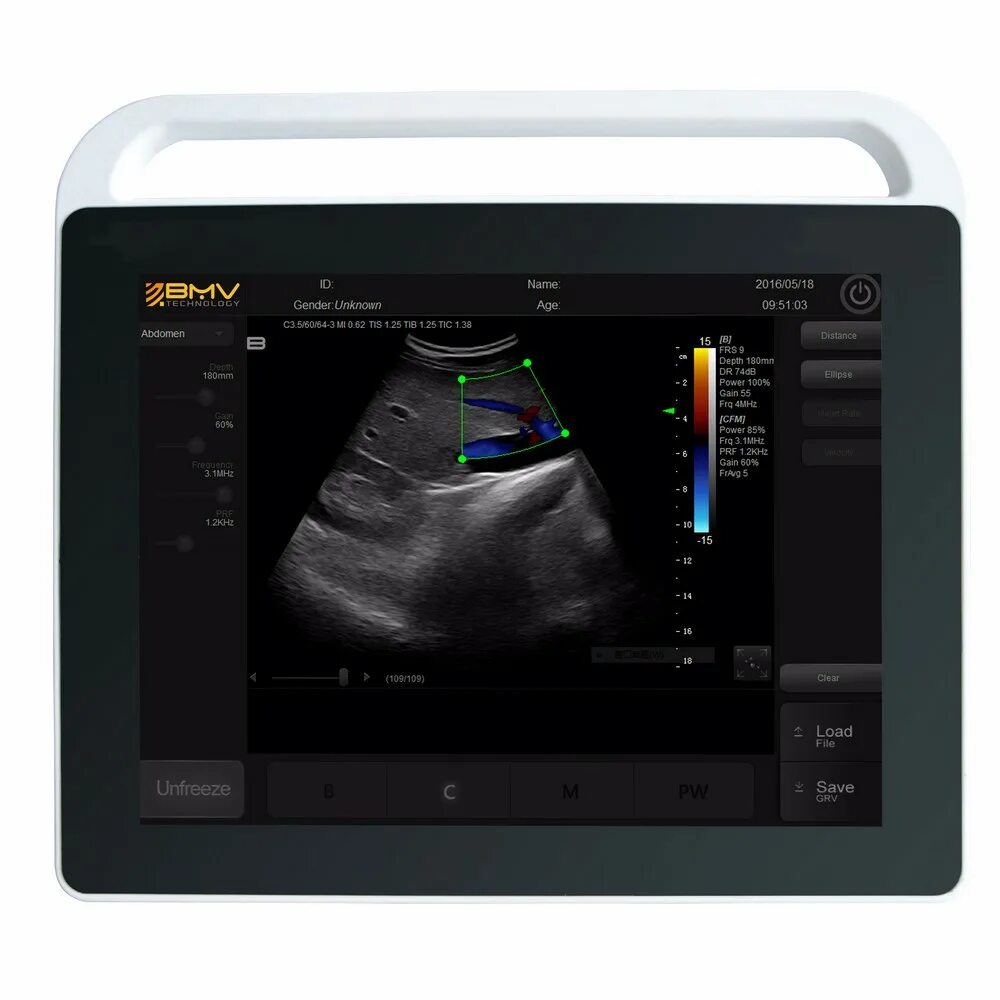

Экран аппарата узи